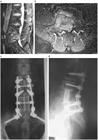

1. がんの既往のある患者が脊椎に痛みを訴えた場合、転移性脊椎腫瘍を念頭に置くことが推奨される(推奨度1)

1. 転移性脊椎腫瘍を疑った場合、全身の造影CTを撮影することが推奨される(推奨度1)

1. 転移性脊椎腫瘍と診断した場合、余命を評価することが推奨される(推奨度1)